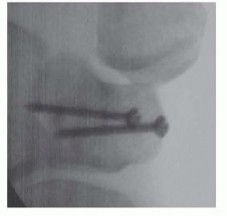

Image

Definitive fixation is optimally achieved using headless compression screws. For capitate neck fractures, an antegrade trajectory (from the dorsal proximal pole directed distally into the body) or a retrograde trajectory (from the dorsal body directed proximally into the head) can be utilized, depending on fracture morphology and fragment size. The screw must be entirely buried beneath the articular cartilage to prevent devastating midcarpal impingement. Intraoperative fluoroscopy is utilized continuously to confirm anatomic reduction, verify screw length, and ensure no hardware penetrates the articular surfaces. If comminution is severe, supplemental K-wire fixation or even a miniature dorsal spanning plate may be required.